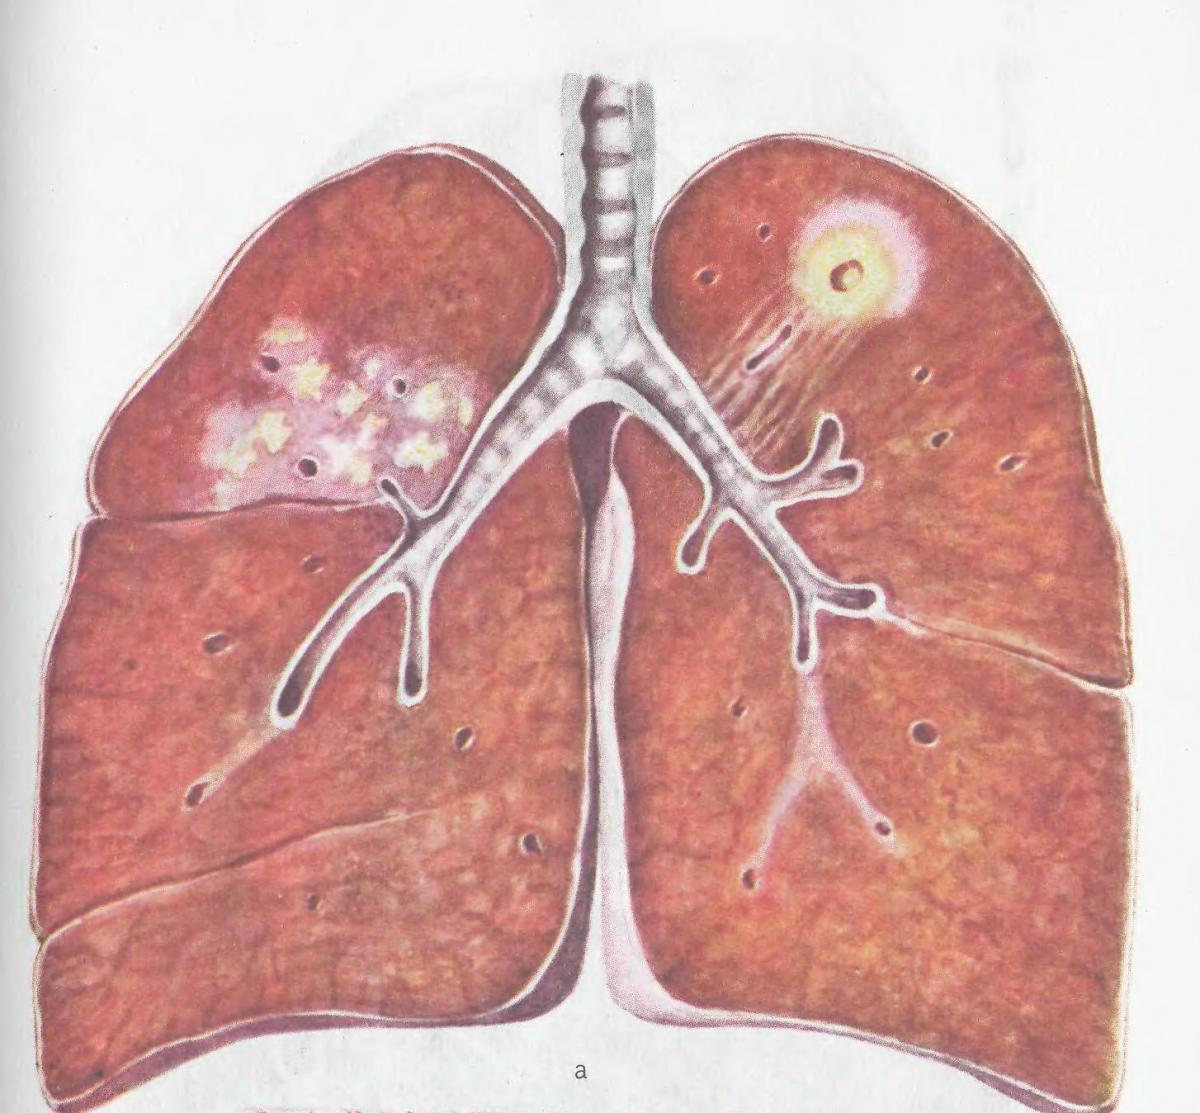

Медицинская тема: легочные осложнения при пневмонии